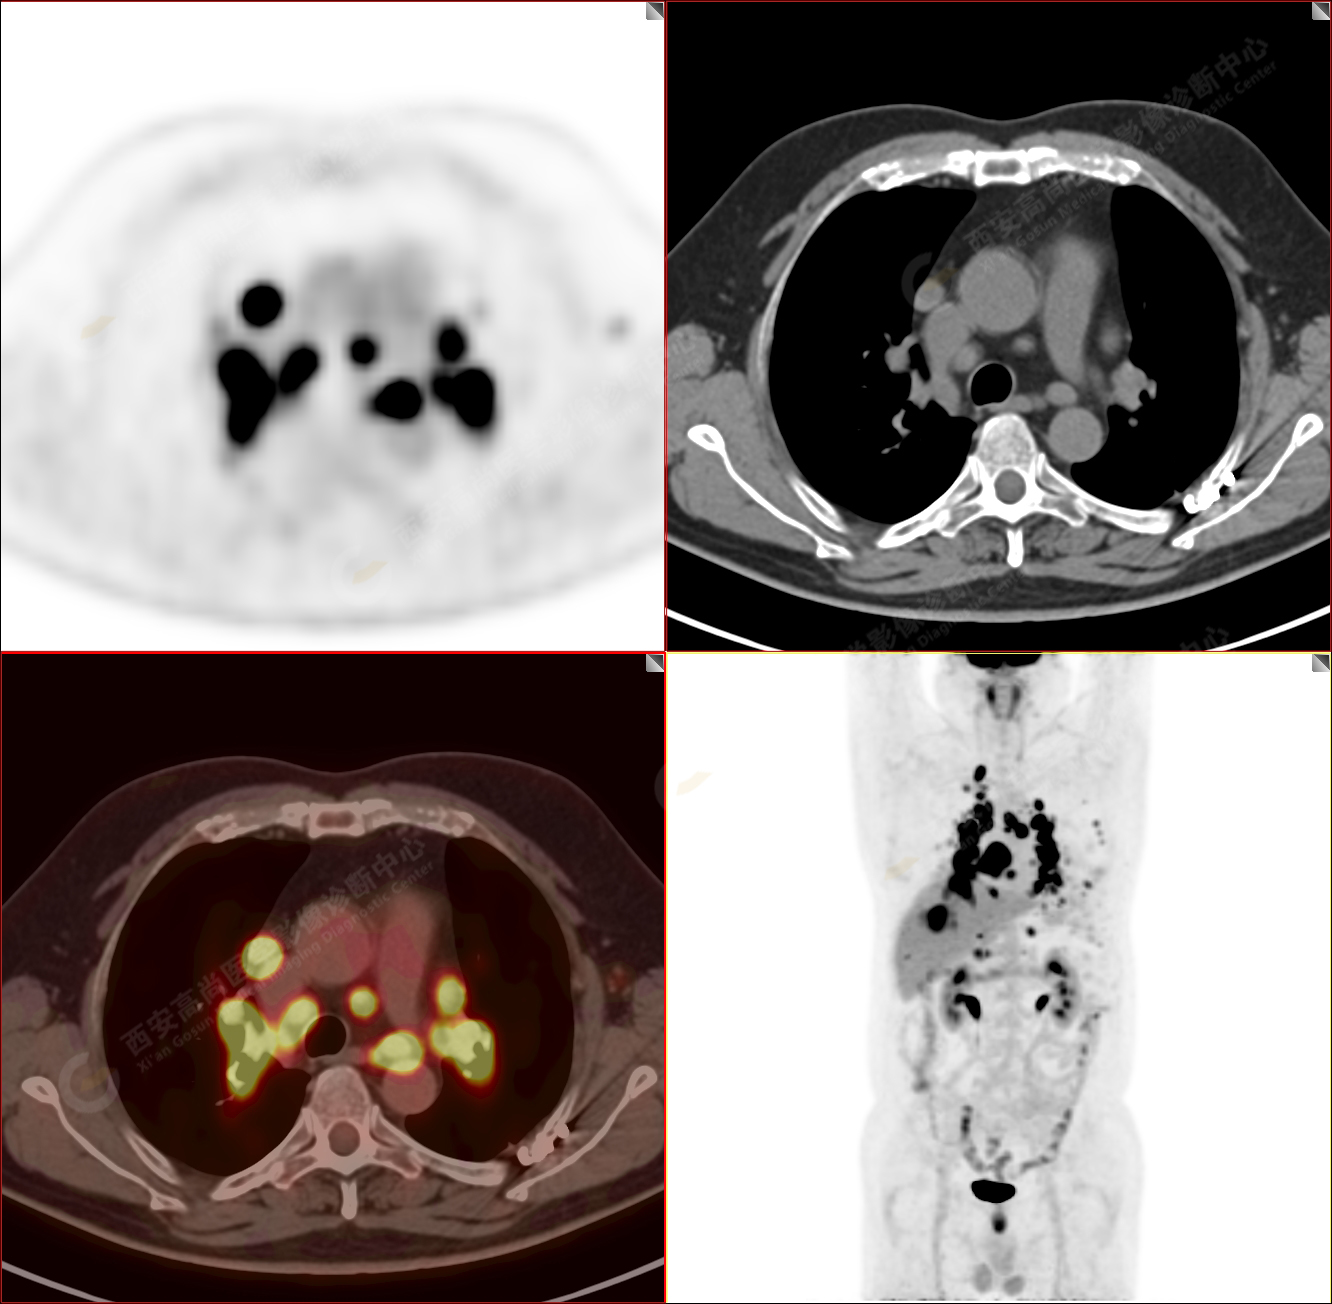

男性,53歲,頭暈半月入院,CT發(fā)現(xiàn)肺內(nèi)腫塊,雙肺多發(fā)大小不等實性及粟粒樣結(jié)節(jié),雙肺門及縱隔多發(fā)腫大淋巴結(jié)。病程中無發(fā)熱、胸悶氣及胸部不適。既往:左側(cè)肋骨外傷史。

PET/CT圖像

PET-MR圖像